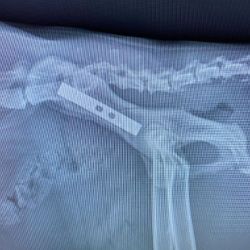

Chirurgie orthopédique et traumatologique

Chirurgie du genou, TPLO